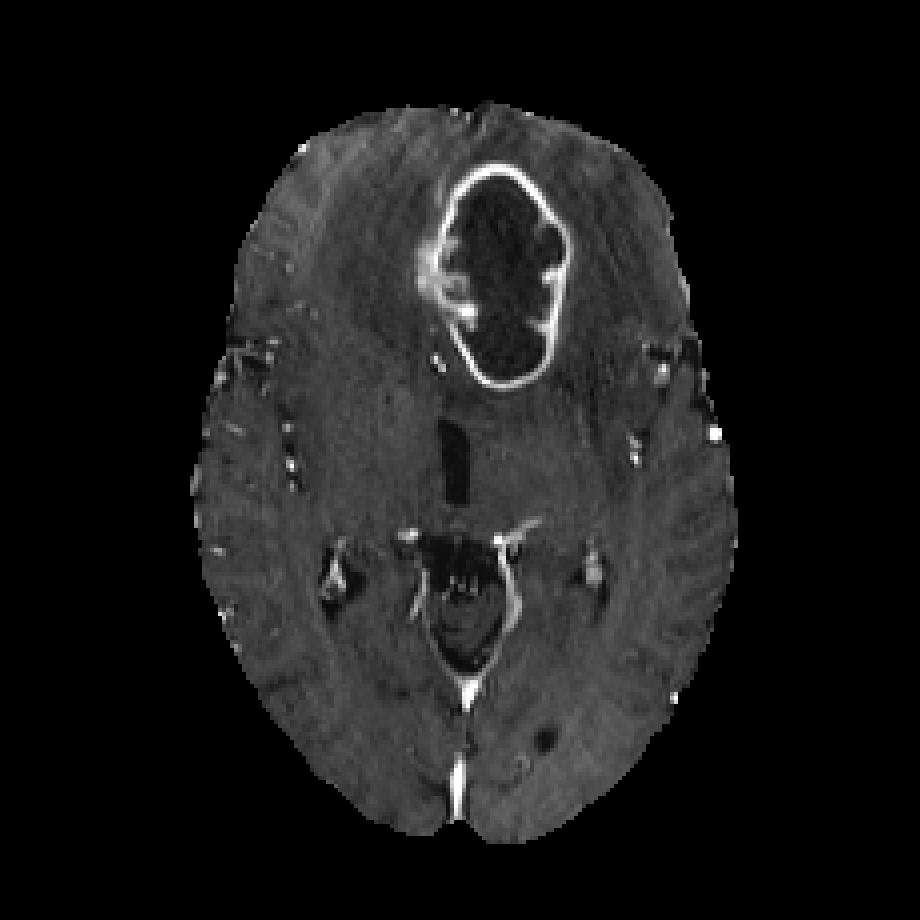

Multimodal medical image segmentation approaches are commonly designed with an end-to-end scheme to learn intermodal associations (Isensee et al., 2018; Zhang et al., 2021a, b; Zhou et al., 2020a, 2022; Ding et al., 2021; Dolz et al., 2018). Certain medical conditions (Figure 2) require segmentor to simultaneously identify multiple regions, such as the tumors, edemas, and necrotic tumor cores. We then refer to the end-to-end learning scheme above as joint learning, as it jointly maps multimodal inputs to single or multiple regions. The joint learning method typically involves fusing multimodal image encoding into a deep encoder-decoder architecture, which outputs the segmentation(s). These methods can be broadly classified into early fusion and mid-term fusion. The former directly concatenates multimodal images as input to the network (Oktay et al., 2018; Isensee et al., 2018; Zhang et al., 2021b; Hatamizadeh et al., 2022; Mai et al., 2022). While the latter uses modality-specific encoders to extract individual features that are later combined in the middle layers of the network and share the same decoder (Xing et al., 2022; Zhang et al., 2021a; Ding et al., 2021; Zhou et al., 2020a, 2022; Dolz et al., 2018).

Furthermore, experienced radiologists often analyze multimodal data in clinical practice by designating a primary modality and several auxiliary modalities for pathological diagnosis. This approach is exemplified in the BraTS challenge (Menze et al., 2014) (Figure 2). In this challenge, the segmentation target was the different areas of glioblastoma, which is the most common type of brain malignancy. Glioblastoma is characterized by its resistance to treatment and poor prognosis, making it a critical focus for advancements in medical imaging and treatment strategies(Li et al., 2019). Human annotators primarily employ the T2 modality222T1, T1CE, T2, and FLAIR represent four modalities generated by MRI imaging technology. for segmenting the edema region while using the FLAIR modality to verify the presence of edema and other fluid-filled structures. Subsequently, the tumor core (TC) is identified through the combined use of T1CE and T1 modalities. The expertise of these radiologists suggests that specific mapping relationships exist between modalities and target areas. Certain modalities facilitate the identification of particular area boundaries, while others serve as supplementary aids. Gleaning insights from this expert knowledge and incorporating it as an inductive bias can potentially reduce the complexity of learning relationships between modalities and corresponding regions. A similar example of adding priors to reduce learning difficulty is DetexNet (Liu et al., 2020), which simplifies low-level representation patterns by embedding expert knowledge.